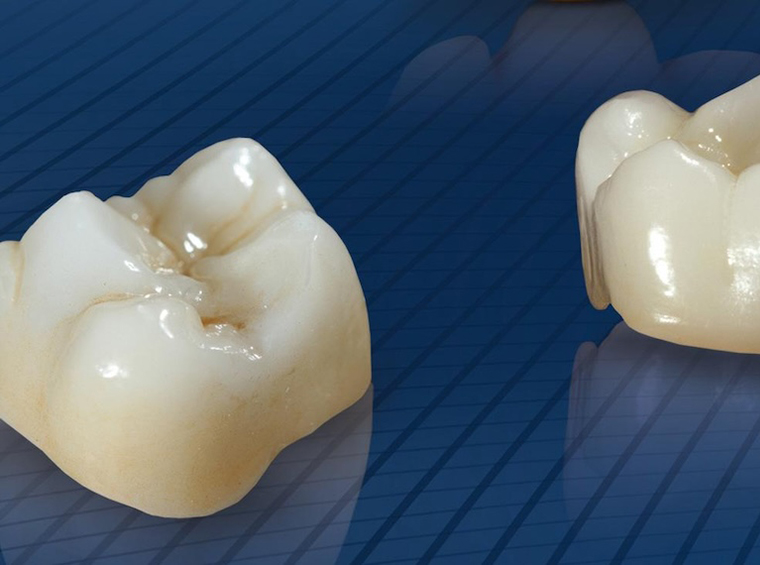

セレック(CEREC)

質の高いセラミックで即日治療

歯の詰め物・被せ物では、1世紀以上の歴史がある世界的な医療メーカーの手がける「セレック(CEREC)」により、質の高いセラミックで即日治療を実現します。

治療部分の衛生面が保たれるだけでなく、治療時間、通院回数を削減します。